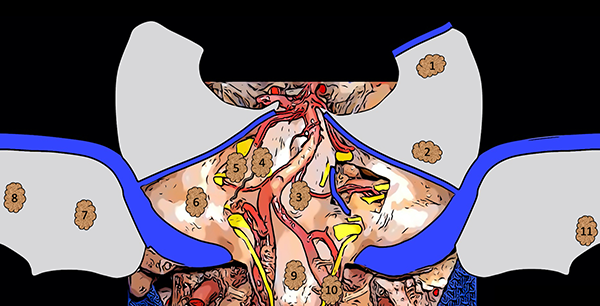

La figura 12 es un dibujo esquemático que sintetiza la presente clasificación (Figura 12).

Figura 12. Dibujo esquemático de la clasificación de los meningiomas de fosa posterior. 1: Meningioma tentorial medial; 2: Meningioma tentorial lateral; 3: Meningioma clival; 4: Meningioma petro-clival; 5: Meningioma petroso anterior; 6: Meningioma petroso posterior; 7: Meningioma de la convexidad lateral; 8: Meningioma de la convexidad medial; 9: Meningioma del foramen magno anterior; 10: Meningioma del foramen magno lateral; 11: Meningioma del foramen magno posterior.